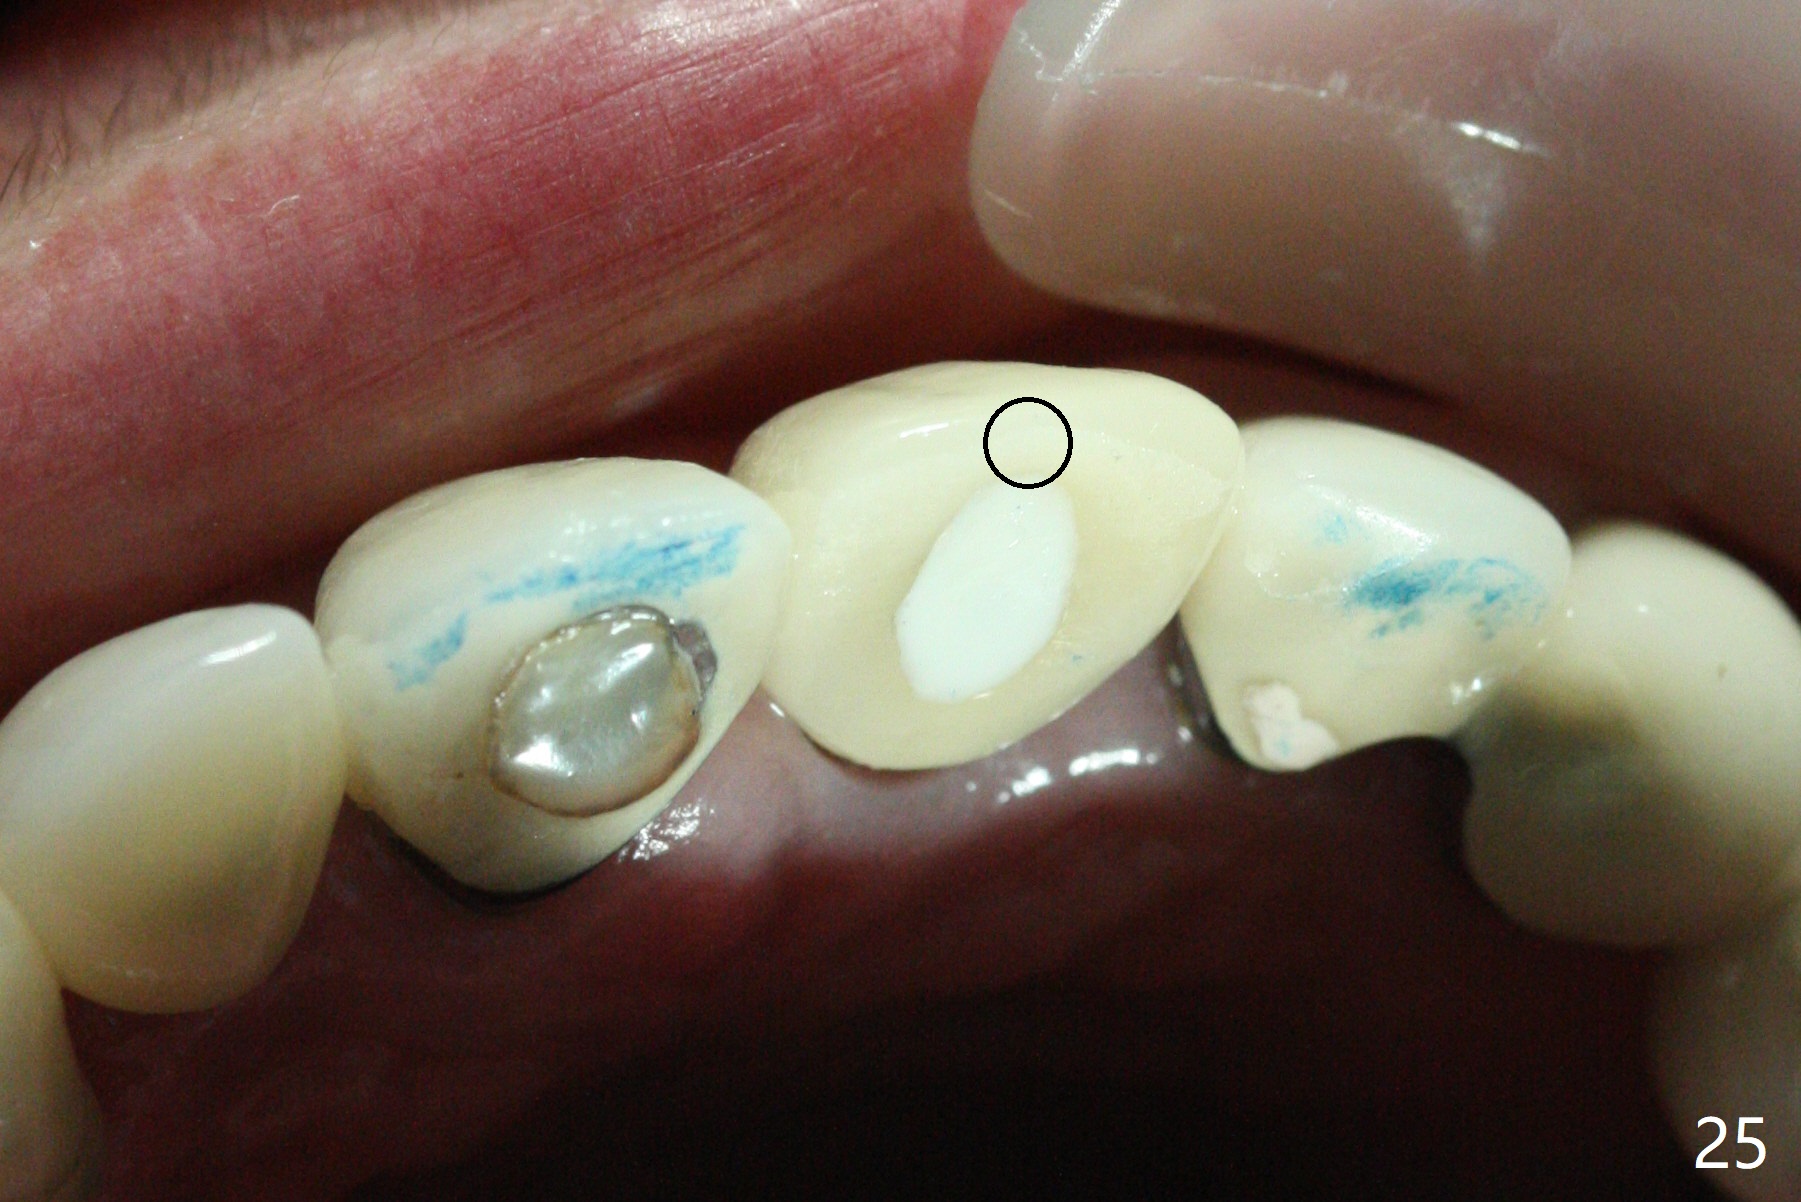

The buccal contour at #9 seems to be slightly concave preop (Fig.1,2 (*)). In fact the buccal plate is found to be lost when the tooth is extracted. Osteotomy is initiated as palatal as possible apical, but the occlusion dictates the coronal end of the osteotomy should be buccal, leaving the buccal gap ~ 2 mm for bone graft. The initial osteotomy (18 mm deep) appears to be close to the Incisive Foramen (Fig.3 blue dashed line). The nasal floor appears to be intact when the drill is removed. Subsequent osteotomy is adjusted so that the apical end of the osteotomy moves distal; when a 3.8x15 mm dummy implant is partially placed, there is clearance (Fig.4). It remains so when a definitive implant is seated (Fig.5); Vanilla graft is placed (Fig.5 *) before placement of a 4.5x5.5(3) mm abutment. More allograft is placed when an immediate provisional is fabricated (Fig.6 arrow and *). The gingiva remains to be recessive 1 month postop (Fig.7). It seems to be related to the bulky gingival margin of the provisional (Fig.8 *). After trimming the latter (Fig.9 *), the gingival margin immediately returns close to normal (Fig.10). The gingival margin is even between #8 and 9 two months postop, but the bone graft is exposed apically (Fig.11 ^). It may heals by itself. Otherwise debridement, regraft, PRF and suture are pending. The coronal portion of the socket heals 4 months postop (Fig.12). The gingival cuff forms by the immediate provisional (which is removed for impression) 4 months postop (Fig.13 *). While the full Zirconia crown at #7 remains intact (Fig.14), the PFM at #9 has porcelain chip (Fig.15). It is partially due to the occlusion; while the crown at #7 has clearance with the opposing dentition (Fig.16 *), the one at #9 has no. The access hole at #9 (Fig.17 *) seems to weaken the crown structure. There is no access hole at #7. No solid posterior support is another contributing factor for chip (Fig.18). The buccal plate has mild atrophy at #7 and 9 (Fig.19 *). A piece of bone graft is being expelled apically at #9 (Fig.20 >) and is removed subsequently (Fig.21). Before impression for repacking porcelain, the opposing incisal edge has been shortened (Fig.22 arrows, as compared to Fig.16). Since the ideal access hole is at the incisal edge (Fig.25 black circle), buccal to the existing one (Fig.24 A), the abutment is torqued before the repaired crown is recemented (Fig.23). Finally the crown has occlusal clearance (Fig.26). Porcelain chips again around the access hole of PFM 1.5 years post 2nd cementation. The dense bone at the crest (*) cannot explain why the abutment is not loose, since it remains incompletely seated (>). As it was trimmed short, an angled abutment is used (Fig.28). The coronal end is lingual, while #9/24 is edge to edge. The lingual aspect of the coronal end of the abutment is heavily trimmed to reduce bulkiness. To prevent chip, Zirconium crown will be fabricated in spite of the fact that it does not match the PFM of #8 (potential shade discrepancy). The patient is pleased with the new Zirconia crown (Fig.29).